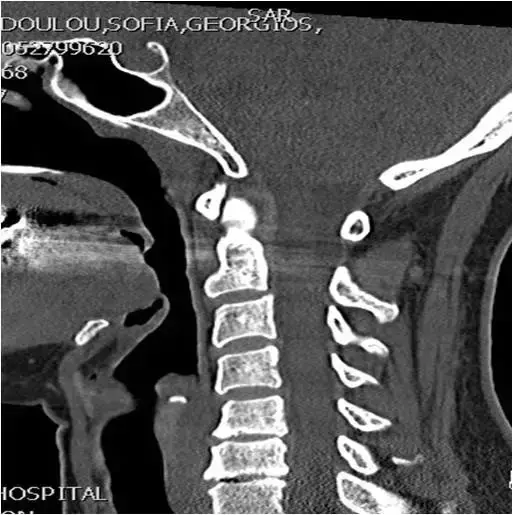

图17:颈椎CT扫描。矢状位重建。C5相对于C4椎骨的轻度后移位。C5-C6关节间隙狭窄,轻度终板硬化和同一水平的小前骨赘。像。

图18:在钩突关节间隙水平处上颈椎的轴向CT图像。